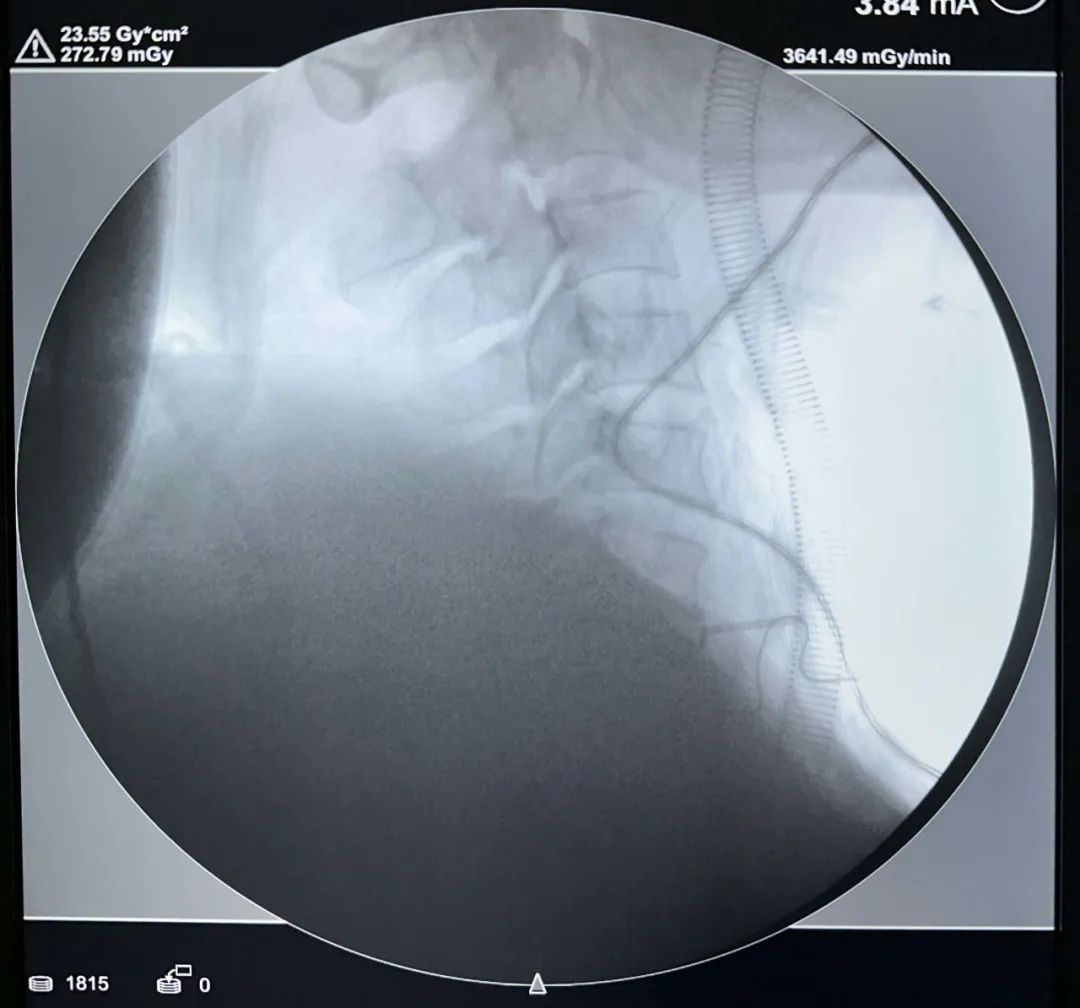

術(shù)中影像

術(shù)區(qū)暴露——

責(zé)任間盤(pán)處理——

融合器準(zhǔn)備——

融合器打入及確認(rèn)——